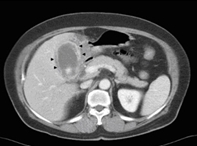

정확한 진단이 어려운 경우

복부 전산화 단층촬영(CT)을 하여 급성 담낭염을 진단하고,

합병증 또는 췌장이나 담관 등 다른 복강 내 병변을 확인합니다.